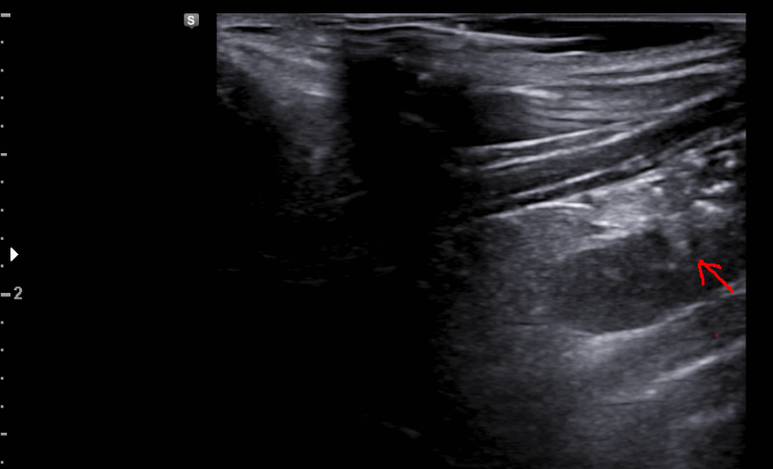

갑상선 실질이 거칠어지고 저음영의 미세결절들이 증가되어 관찰

저음영의 미세결절 변화는 매우 두드러지고 갑상선 비대해짐

갑상선염 소견 진행

도플러 패턴도 강해짐